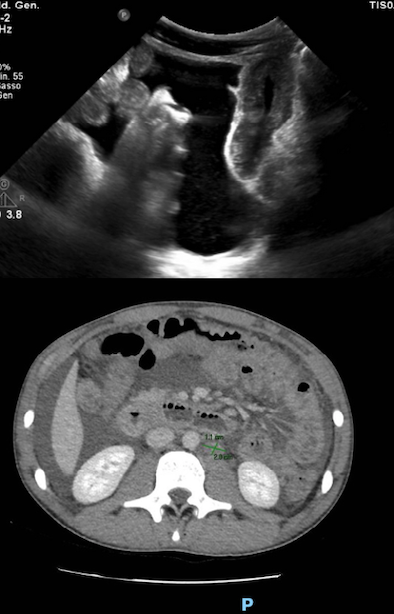

L’ecografia addominale evidenziava la presenza di versamento ascitico e un diffuso ispessimento delle pareti intestinali sia tenuali che coliche (max 5 mm), con perdita di stratificazione. La TC addome confermava versamento ascitico esteso con spessore assiale massimo di 10 cm nello scavo pelvico e ispessimento parietale diffuso dal tratto distale dell’esofago fino al tratto prossimale del retto, compatibile con panenterocolite; non mostrava segni di ostruzione intestinale, pneumoperitoneo, masse/pacchetti linfonodali e alterazioni delle strutture vascolari (Figura). Il liquido ascitico prelevato mediante paracentesi eco-guidata mostrava un alto contenuto proteico (> 3 g/dl), una spiccata cellularità di tipo eosinofilo (85%) e risultava sterile dal punto di vista microbiologico. La biopsia osteomidollare evidenziava un midollo ipercellulato con significativa espansione della serie eosinofila (23% della popolazione cellulare) senza caratteristiche morfologiche neoplastiche.